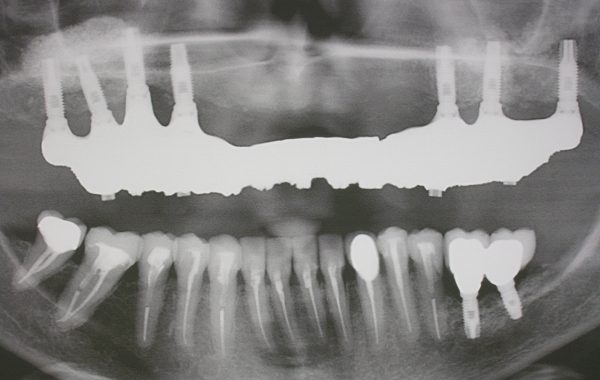

Ahora presentaremos las radiografías de una paciente de 55 años donde se aprecia la falta de hueso por debajo de los senos maxilares debido a la ausencia de los dientes, como mencionamos este proceso de pérdida de hueso es normal y no es patológico. Después apreciamos la radiografía donde se hace el procedimiento de elevación de seno maxilar donde se aprecia la colocación del injerto con los implantes ya colocados.

Nótese el injerto colocado obteniendo mayor altura para la colocación de los implantes